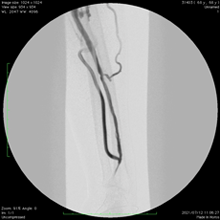

実際の症例①

自己血管シャント狭窄を繰り返し3ヶ月ごとに標準のバルーン拡張術(PTA)を行っていましたが、薬剤コーティングバルーンを併用することで6ヶ月も再狭窄なく透析が可能でした。

3ヶ月ごとに

狭窄繰り返し

バルーン

にて拡張後

再狭窄見られず